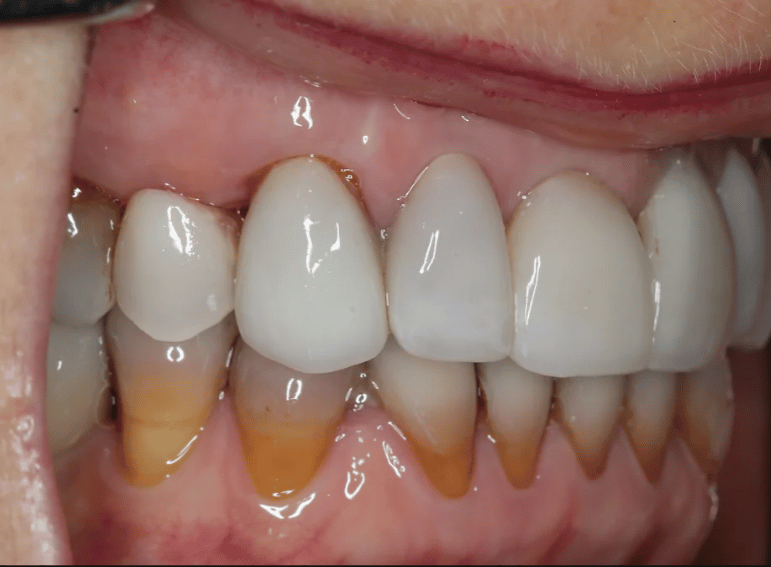

Case 3 – Implants

Removal of a premolar and replacement with an implant.